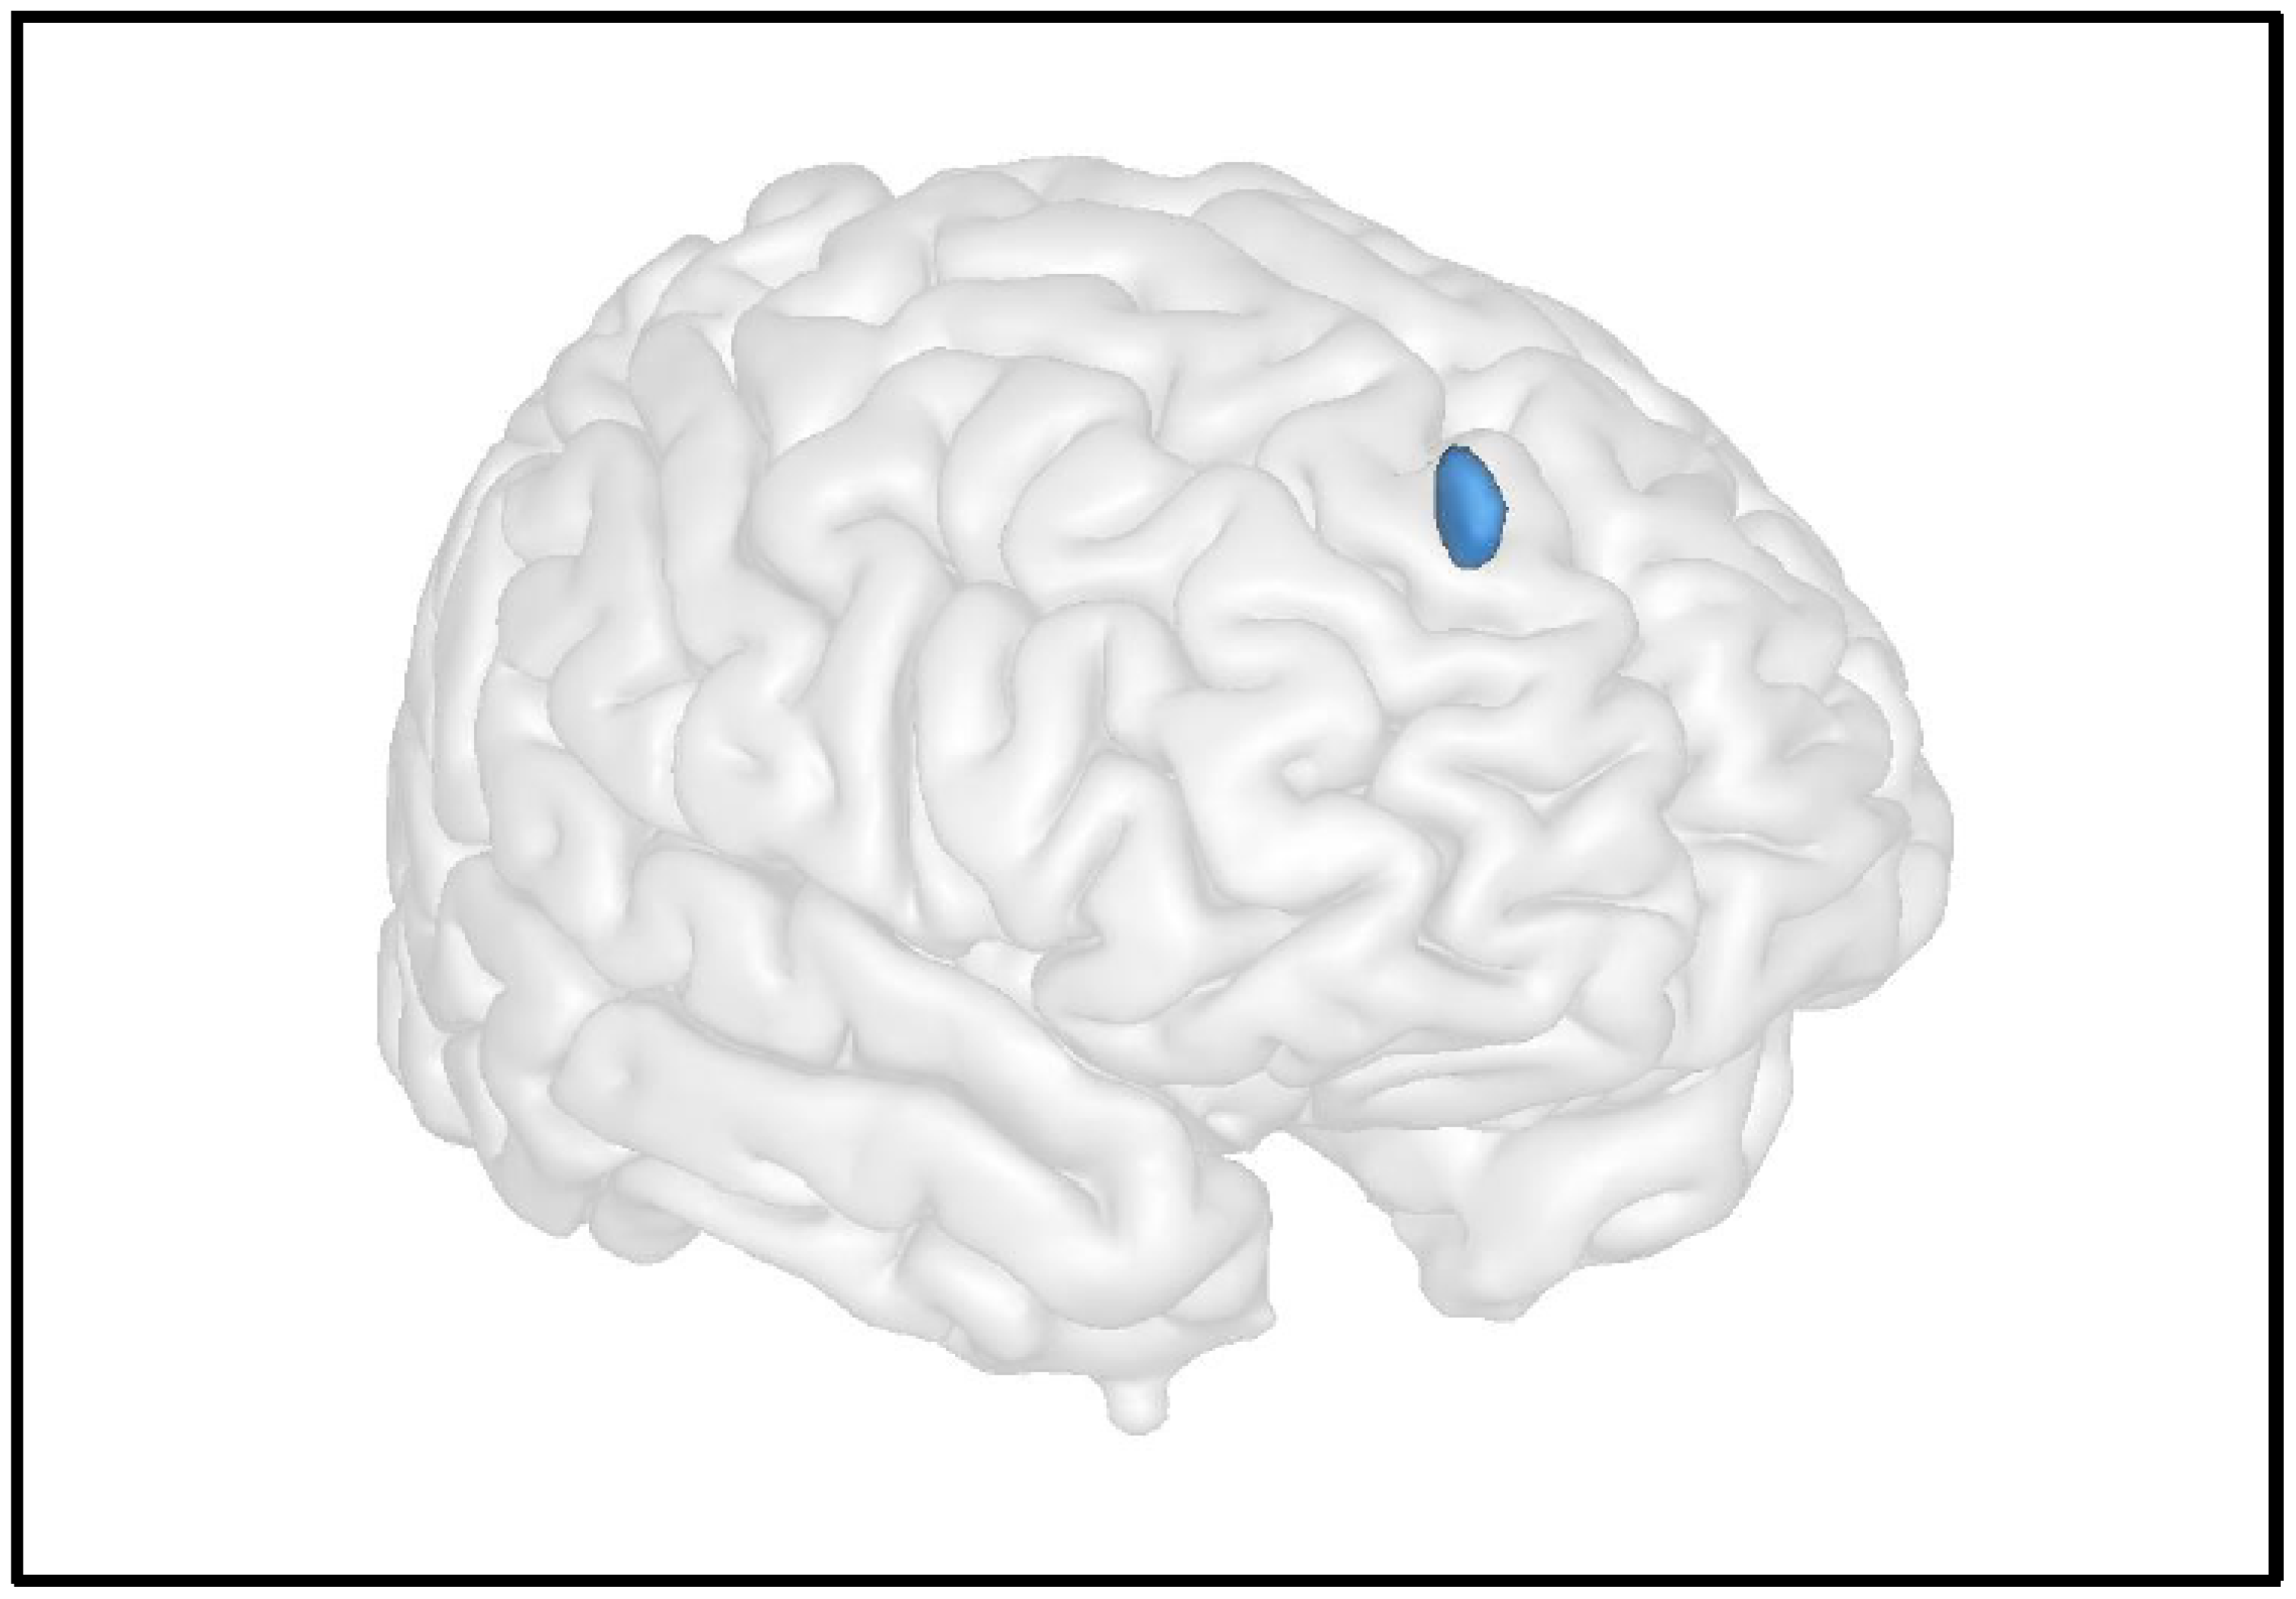

In the only study investigating grey matter abnormalities, we compared anatomical images from cystinosis patients to those from controls with nephropathy and from healthy controls [17]. We used a voxel-based morphometry (VBM) analysis to compare grey matter volume between groups in each and every voxel of the brain. This whole-brain approach allows investigating putative differences in grey matter without an a priori hypothesis. The results showed significantly decreased grey matter in the left middle frontal gyrus in cystinosis patients compared to healthy controls. Interestingly, brain abnormalities within this region could be associated with executive function deficits clinically described in these patients [10,12]. A significant decrease in grey matter in the same region was also observed in controls with nephropathy compared to healthy controls. No significant difference was observed between cystinosis patients and controls with nephropathy, which suggests that these abnormalities may not be specific to cystinosis patients and encourage brain imaging and neurocognitive investigations in a broader range of renal diseases.

The study of resting brain function provides information on the level of activity of the different brain regions as a “baseline”, outside task performance. Using arterial spin labelling MRI (ASL-MRI), cerebral blood flow (CBF) can be measured at the cerebral level using intrinsic physiological contrast by labelling water protons from cervical arteries and measuring them once they are at the cerebral level [49]. In a recent study, we compared arterial spin labelling images between patients with cystinosis and healthy controls, using a whole-brain approach [17]. We did not find any significant differences in resting cerebral blood flow values between groups. However, in cystinosis patients, the results showed a significant negative correlation between the cystine blood level and resting cerebral blood flow in the right superior frontal gyrus (Figure 4). Indeed, patients with higher levels of cystine were those presenting with lower resting cerebral blood flow values in the superior frontal cortex, which reinforces the link between cystinosis disease and abnormalities within frontal brain regions. Importantly, the superior frontal cortex is associated with executive functions, and the described abnormalities could underline the neurocognitive deficits described in cystinosis patients, such as memory impairments or further cognitive impairments.

Figure 4.

Advanced neuroimaging techniques can help in understanding the impact of cystinosis on the brain’s anatomo-function and its link with neurocognitive impairments. For instance, here, we illustrate the results of Scheme 10 (y = 50 z = 40), a brain region strongly implicated in cognitive functions: the higher the cystine levels, the lower the resting CBF in this area, which is associated with cognitive functions. Maximum intensity projections of T statistics clusters that are significantly correlated with individual cystine blood level are superimposed on a 3D volume rendering on grey matter in the MNI space.